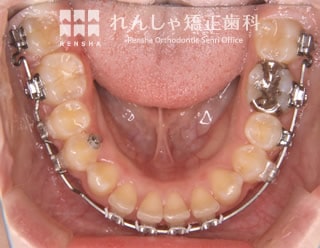

補綴前矯正(26歳 治療期間:2年2か月)

右下の永久歯が先天的に欠損していたため、下前歯は右側に偏っていました。

左側の噛み合わせに大きな問題はなかったことから、右上前歯のがたつきを改善し、右下には1歯分のスペースを確保してインプラント治療を受けていただきました。

| 装置名 | マルチブラケット装置 |